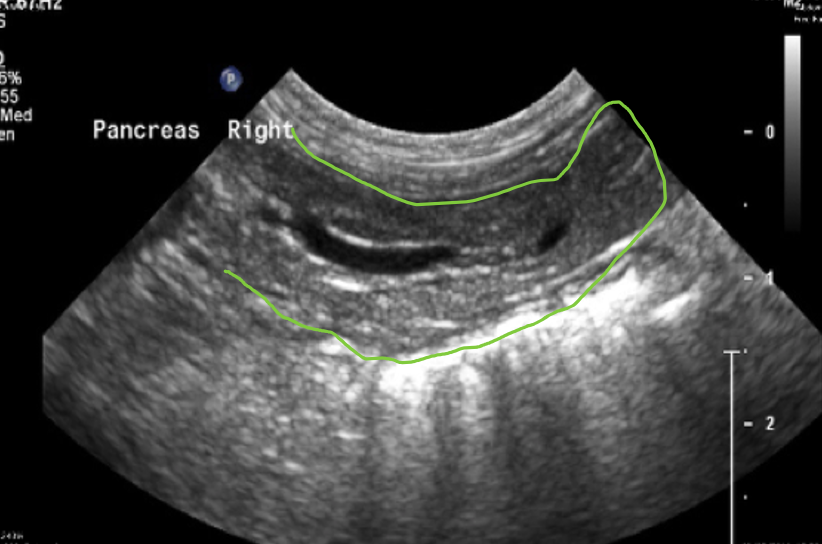

The Right Limb of Pancreas

Scanning from the right underside of the patient (patient in right lateral recumbency position), the long axis section of the right limb of pancreas and the descending duodenum can be seen running horizontally across the screen

- This will bring the long axis of the descending duodenum into view, running horizontally across the near field of the screen. The right limb of the pancreas is attached to the descending duodenum by mesentery and will be lying parallel to this section of the duodenum. Scan in the parasagittal plane through the duodenum to locate the right limb of pancreas in a long axis section.

The long axis section of the right limb of pancreas seen running horizontal across the screen